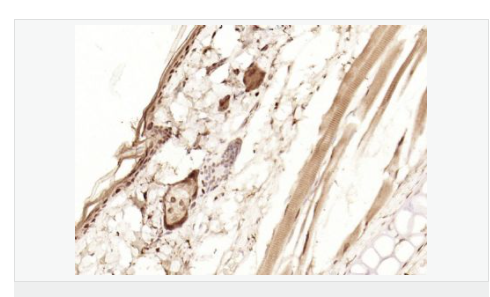

| 產(chǎn)品應(yīng)用 | WB=1:1000-2000 ELISA=1:1000-5000 IHC-P=1:100-500 IHC-F=1:100-500 Flow-Cyt=1ug/Test ICC=1:100-500 IF=1:100-500 (石蠟切片需做抗原修復(fù)) not yet tested in other applications. optimal dilutions/concentrations should be determined by the end user. |

| 細(xì)胞定位 | 細(xì)胞核 細(xì)胞漿 |

| 產(chǎn)品介紹 | p53, a DNA-binding, oligomerization domain- and transcription activation domain-containing tumor suppressor, upregulates growth arrest and apoptosis-related genes in response to stress signals, thereby influencing programmed cell death, cell differentiation, and cell cycle control mechanisms. p53 localizes to the nucleus, yet can be chaperoned to the cytoplasm by the negative regulator, MDM2. MDM2 is an E3 ubiquitin ligase that is upregulated in the presence of active p53, where it poly-ubiquitinates p53 for proteasome targeting. p53 fluctuates between latent and active DNA-binding conformations and is differentially activated through posttranslational modifications, including phosphorylation and acetylation. Mutations in the DNA-binding domain (DBD) of p53, amino acids 110-286, can compromise energetically-favorable association with cis elements and are implicated in several human cancers. Function: [FUNCTION] Acts as a tumor suppressor in many tumor types; induces growth arrest or apoptosis depending on the physiological circumstances and cell type. Involved in cell cycle regulation as a trans-activator that acts to negatively regulate cell division by controlling a set of genes required for this process. One of the activated genes is an inhibitor of cyclin-dependent kinases. Apoptosis induction seems to be mediated either by stimulation of BAX and FAS antigen expression, or by repression of Bcl-2 expression. Implicated in Notch signaling cross-over. Prevents CDK7 kinase activity when associated to CAK complex in response to DNA damage, thus stopping cell cycle progression. Isoform 2 enhances the transactivation activity of isoform 1 from some but not all TP53-inducible promoters. Isoform 4 suppresses transactivation activity and impairs growth suppression mediated by isoform 1. Isoform 7 inhibits isoform 1-mediated apoptosis. Subunit: Interacts with AXIN1. Probably part of a complex consisting of TP53, HIPK2 and AXIN1 (By similarity). Binds DNA as a homotetramer. Interacts with histone acetyltransferases EP300 and methyltransferases HRMT1L2 and CARM1, and recruits them to promoters Subcellular Location: Cytoplasm. Nucleus. Nucleus, PML body. Endoplasmic reticulum. Note=Interaction with BANP promotes nuclear localization. Recruited into PML bodies together with CHEK2. Tissue Specificity: Ubiquitous. Isoforms are expressed in a wide range of normal tissues but in a tissue-dependent manner. Isoform 2 is expressed in most normal tissues but is not detected in brain, lung, prostate, muscle, fetal brain, spinal cord and fetal liver. Isoform 3 is expressed in most normal tissues but is not detected in lung, spleen, testis, fetal brain, spinal cord and fetal liver. Isoform 7 is expressed in most normal tissues but is not detected in prostate, uterus, skeletal muscle and breast. Isoform 8 is detected only in colon, bone marrow, testis, fetal brain and intestine. Isoform 9 is expressed in most normal tissues but is not detected in brain, heart, lung, fetal liver, salivary gland, breast or intestine. Post-translational modifications: Acetylated. Acetylation of Lys-382 by CREBBP enhances transcriptional activity. Deacetylation of Lys-382 by SIRT1 impairs its ability to induce proapoptotic program and modulate cell senescence. Phosphorylation on Ser residues mediates transcriptional activation. Phosphorylated by HIPK1. Phosphorylation at Ser-9 by HIPK4 increases repression activity on BIRC5 promoter. Phosphorylated on Thr-18 by VRK1. Phosphorylated on Ser-20 by CHEK2 in response to DNA damage, which prevents ubiquitination by MDM2. Phosphorylated on Ser-20 by PLK3 in response to reactive oxygen species (ROS), promoting p53/TP53-mediated apoptosis. Phosphorylated on Thr-55 by TAF1, which promotes MDM2-mediated degradation. Phosphorylated on Ser-33 by CDK7 in a CAK complex in response to DNA damage. Phosphorylated on Ser-46 by HIPK2 upon UV irradiation. Phosphorylation on Ser-46 is required for acetylation by CREBBP. Phosphorylated on Ser-392 following UV but not gamma irradiation. Phosphorylated upon DNA damage, probably by ATM or ATR. Phosphorylated on Ser-15 upon ultraviolet irradiation; which is enhanced by interaction with BANP. Phosphorylated by NUAK1 at Ser-15 and Ser-392; was initially thought to be mediated by STK11/LKB1 but it was later shown that it is indirect and that STK11/LKB1-dependent phosphorylation is probably mediated by downstream NUAK1 (PubMed:21317932). It is unclear whether AMP directly mediates phosphorylation at Ser-15. Phosphorylated on Thr-18 by isoform 1 and isoform 2 of VRK2. Phosphorylation on Thr-18 by isoform 2 of VRK2 results in a reduction in ubiquitination by MDM2 and an increase in acetylation by EP300. Stabilized by CDK5-mediated phosphorylation in response to genotoxic and oxidative stresses at Ser-15, Ser-33 and Ser-46, leading to accumulation of p53/TP53, particularly in the nucleus, thus inducing the transactivation of p53/TP53 target genes. Phosphorylated at Ser-315 and Ser-392 by CDK2 in response to DNA-damage. Dephosphorylated by PP2A-PPP2R5C holoenzyme at Thr-55. SV40 small T antigen inhibits the dephosphorylation by the AC form of PP2A. May be O-glycosylated in the C-terminal basic region. Studied in EB-1 cell line. Ubiquitinated by MDM2 and SYVN1, which leads to proteasomal degradation. Ubiquitinated by RFWD3, which works in cooperation with MDM2 and may catalyze the formation of short polyubiquitin chains on p53/TP53 that are not targeted to the proteasome. Ubiquitinated by MKRN1 at Lys-291 and Lys-292, which leads to proteasomal degradation. Deubiquitinated by USP10, leading to its stabilization. Ubiquitinated by TRIM24, which leads to proteasomal degradation. Ubiquitination by TOPORS induces degradation. Deubiquitination by USP7, leading to stabilization. Isoform 4 is monoubiquitinated in an MDM2-independent manner. Monomethylated at Lys-372 by SETD7, leading to stabilization and increased transcriptional activation. Monomethylated at Lys-370 by SMYD2, leading to decreased DNA-binding activity and subsequent transcriptional regulation activity. Lys-372 monomethylation prevents interaction with SMYD2 and subsequent monomethylation at Lys-370. Dimethylated at Lys-373 by EHMT1 and EHMT2. Monomethylated at Lys-382 by SETD8, promoting interaction with L3MBTL1 and leading to repress transcriptional activity. Demethylation of dimethylated Lys-370 by KDM1A prevents interaction with TP53BP1 and represses TP53-mediated transcriptional activation. Sumoylated by SUMO1. DISEASE: Note=TP53 is found in increased amounts in a wide variety of transformed cells. TP53 is frequently mutated or inactivated in about 60% of cancers. TP53 defects are found in Barrett metaplasia a condition in which the normally stratified squamous epithelium of the lower esophagus is replaced by a metaplastic columnar epithelium. The condition develops as a complication in approximately 10% of patients with chronic gastroesophageal reflux disease and predisposes to the development of esophageal adenocarcinoma. Similarity: Belongs to the p53 family. SWISS: P04637 Gene ID: 7157 Database links: Entrez Gene: 7157 Human Entrez Gene: 22059 Mouse Omim: 191170 Human SwissProt: P04637 Human SwissProt: P02340 Mouse Unigene: 654481 Human Unigene: 222 Mouse Unigene: 54443 Rat Important Note: This product as supplied is intended for research use only, not for use in human, therapeutic or diagnostic applications. |